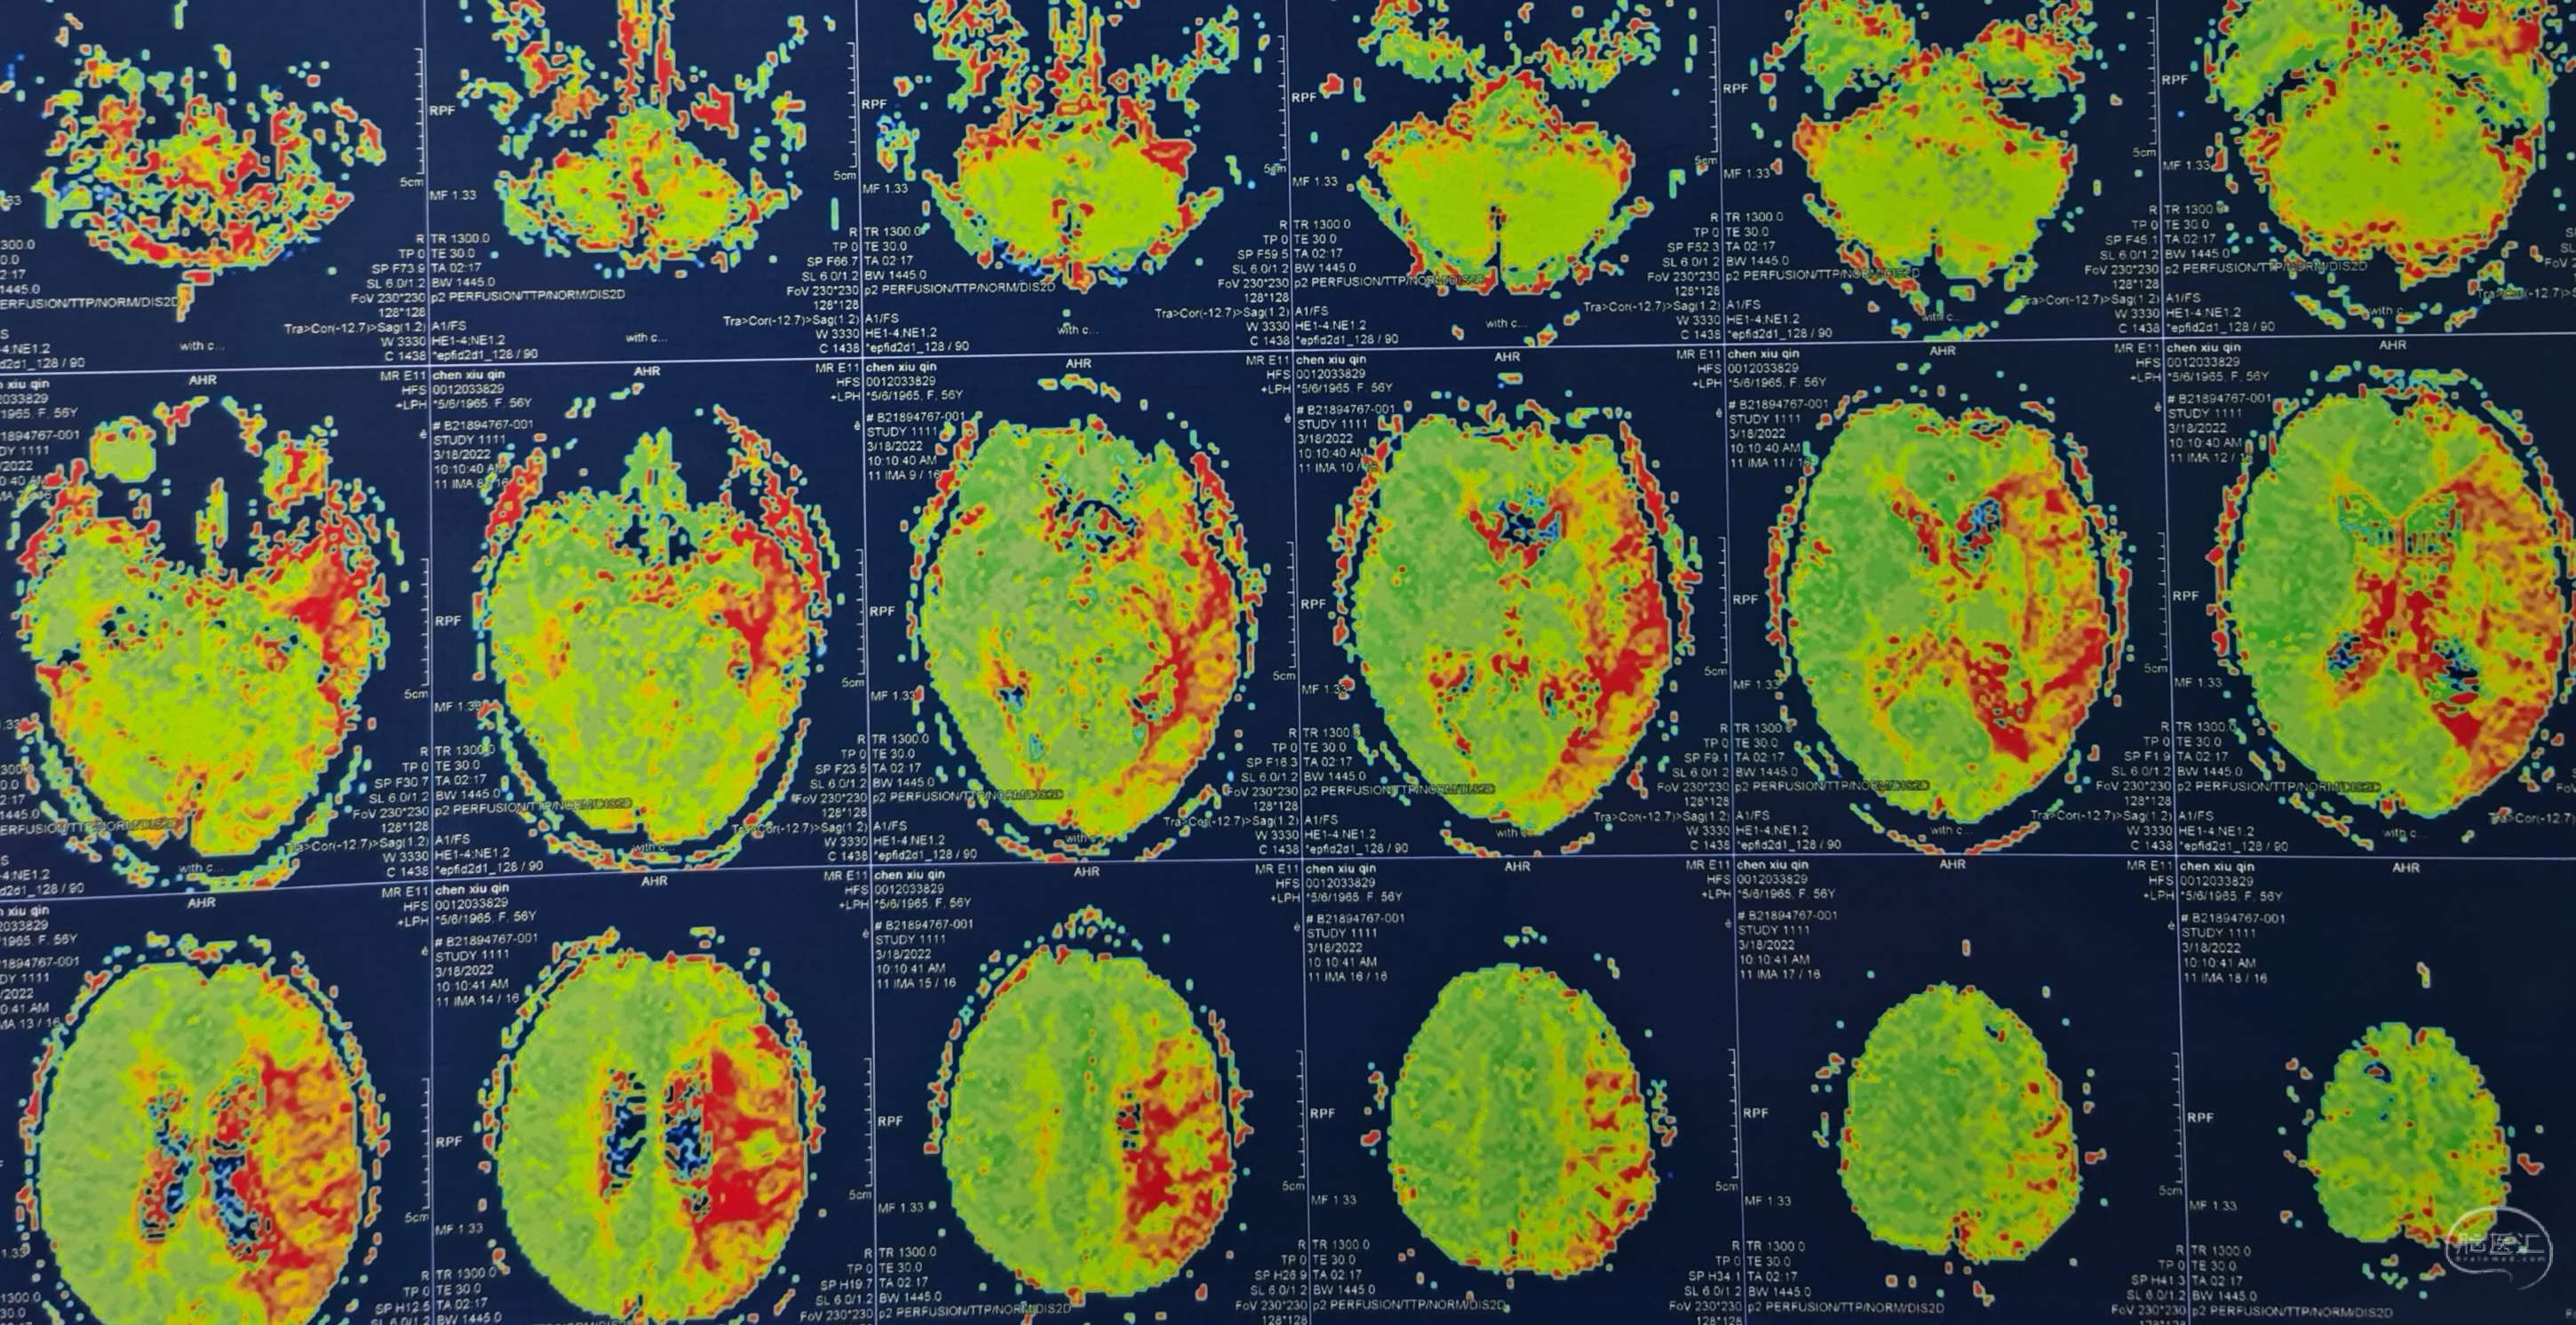

病例6 中年男性,因头昏、一侧肢体无力三月入院。诊断:烟雾病。

脑灌注提示:双侧大脑半球低灌注缺血。

DSA:左侧大脑中动脉、大脑前动脉闭塞,烟雾样血管形成。

颞浅动脉未向颅内代偿。

行颞浅动脉-M4端侧吻合。

吻合14针。

荧光造影示:吻合桥动脉通畅。

病例7 中年男性,因头痛、记忆力下降半年入院。诊断:烟雾病。

脑灌注提示:双侧大脑半球低灌注缺血。

DSA:右侧大脑中动脉、大脑前动脉闭塞,烟雾样血管形成。

颞浅动脉未向颅内代偿。

行颞浅动脉-M4端侧吻合。

吻合14针。

荧光造影示:吻合桥动脉通畅。

病例8 中年女性,因言语不利、反应迟钝1年入院。诊断:烟雾病。

脑灌注提示:双侧大脑半球低灌注缺血。

DSA:左侧大脑中动脉、大脑前动脉闭塞,烟雾样血管形成。

颞浅动脉未向颅内代偿。

行颞浅动脉-M4端侧吻合。

吻合16针。

荧光造影示:吻合桥动脉通畅。